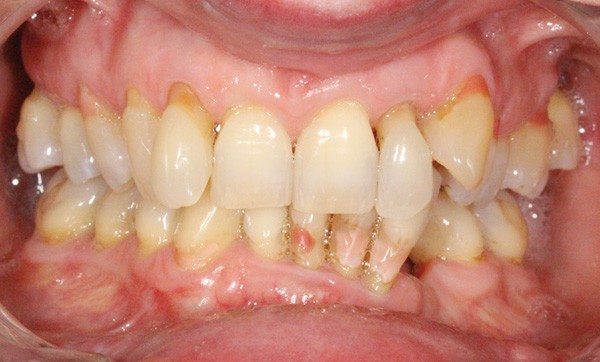

Sur le plan parodontal, la patiente présente une parodontite chronique stabilisée généralisée modérée à sévère (fig. 9).